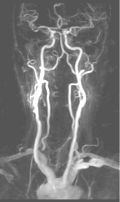

CE-MRA of the aortic arch and great vessels (left) into the brain, renal arteries (top), selective carotid bifurcation (top right) showing ICA/ECA stenosis, and 3-section run-off (very right) showing multiple stenoses, including long-segment bilateral SFA stenoses.

CE-MRA is a fairly new, non-invasive MR technique that utilizes ultra fast MR sequences to obtain exquisite MRA images. These images are obtained during intravenous administration of only 20-30 cc of Gadolinium using an MR-compatible power injector. A bolus-tracking software tracks the bolus of contrast for optimal timing. Subtraction techniques may also be utilized for improved tissue contrast. Thus, a high-end scanner is required to perform the procedure.

The actual scan is performed in one breath hold (about 20 seconds), but of course it takes some time to prepare the patient and set up the protocols. The whole procedure can be performed in ½ hour. 4D reconstruction is then performed.

It is extremely accurate when performed properly, and it correlates well with x-ray angiography and can replace it in many instances. Some patients may undergo surgery based on CE-MRA without the need for conventional angiography. 4D reconstruction allows visualization at multiple angles. Best of all, it is non-invasive!